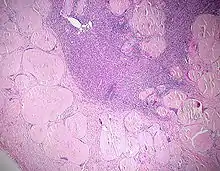

Ausgeprägte Amyloidablagerungen (homogen rosa) in einem Lymphknoten, H&E.

Amyloidablagerungen in den Gefäßwänden, H&E.